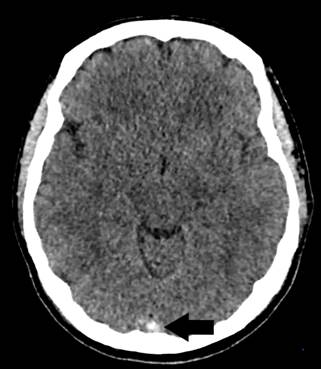

Paciente de 52 años de edad con antecedente de hipertrigliceridemia familiar que ingresa a nuestra institución por cuadro de neumonía bilateral por COVID-19. Al sexto día de internación (y día 16 desde la fecha de inicio de síntomas) evoluciona con cefalea y náuseas y 24 horas después presenta crisis tónico clónica generalizada y deterioro posterior del sensorio con requerimiento de intubación orotraqueal, por lo cual se inicia tratamiento con levetiracetam. Requiere asistencia respiratoria mecánica durante 7 días. Se realiza angioTC de vasos intracraneales que evidencia trombosis a nivel de la prensa de Herófilo, seno transverso, vena anastomótica de Labbé y vena yugular derecha. Se inicia anticoagulación con enoxaparina en dosis de 1 mg/kg cada 12 horas. En exámenes de laboratorio presenta los siguientes valores: ferritina 2933 ng/mL (valor normal 4.6 -204 ng/mL), eritrosedimentación 1ª hora 67 mm (valor normal menor a 20 mm), proteína C reactiva (PCR) cuantitativa 5.9 mg/dL (valor normal menor a 0.8 mg/dL), LDH 451 U/L (valor normal 125 -220 U/L), anticuerpos anticardiolipina IgM 15 MPL e IgG 1 GPL (valor normal menor a 10), anticuerpos anti β2-glicoproteína IgG e IgM 1 U/mL (valor normal menor a 5), factor V Leiden negativo y homocisteinemia 8 µmol/L (valor normal 5 - 15 µmol/L), recuento plaquetario en valores normales durante toda la internación y nivel de actividad anti-Xa posterior al inicio del tratamiento con HBPM de 1,28 U/mL. Intercurre con fibrilación auricular de alta respuesta ventricular que requiere tratamiento con amiodarona. Posterior a la extubación comienza a referir trastornos visuales transitorios, y en su examen neurológico se evidencia dismetría en prueba índice-nariz derecha. En dicho contexto se realiza RMN de cerebro que evidencia lesiones isquémicas en hemisferio cerebeloso derecho y región occipital izquierda en relación al territorio vascular venoso comprometido. Evoluciona favorablemente con estabilidad desde el punto de vista clínico y neurológico, y egresa con tratamiento con acenocumarol.

Figura 1. TC cerebro sin contraste corte axial que evidencia imagen espontáneamente densa a nivel de la prensa de Herófilo (flecha negra)